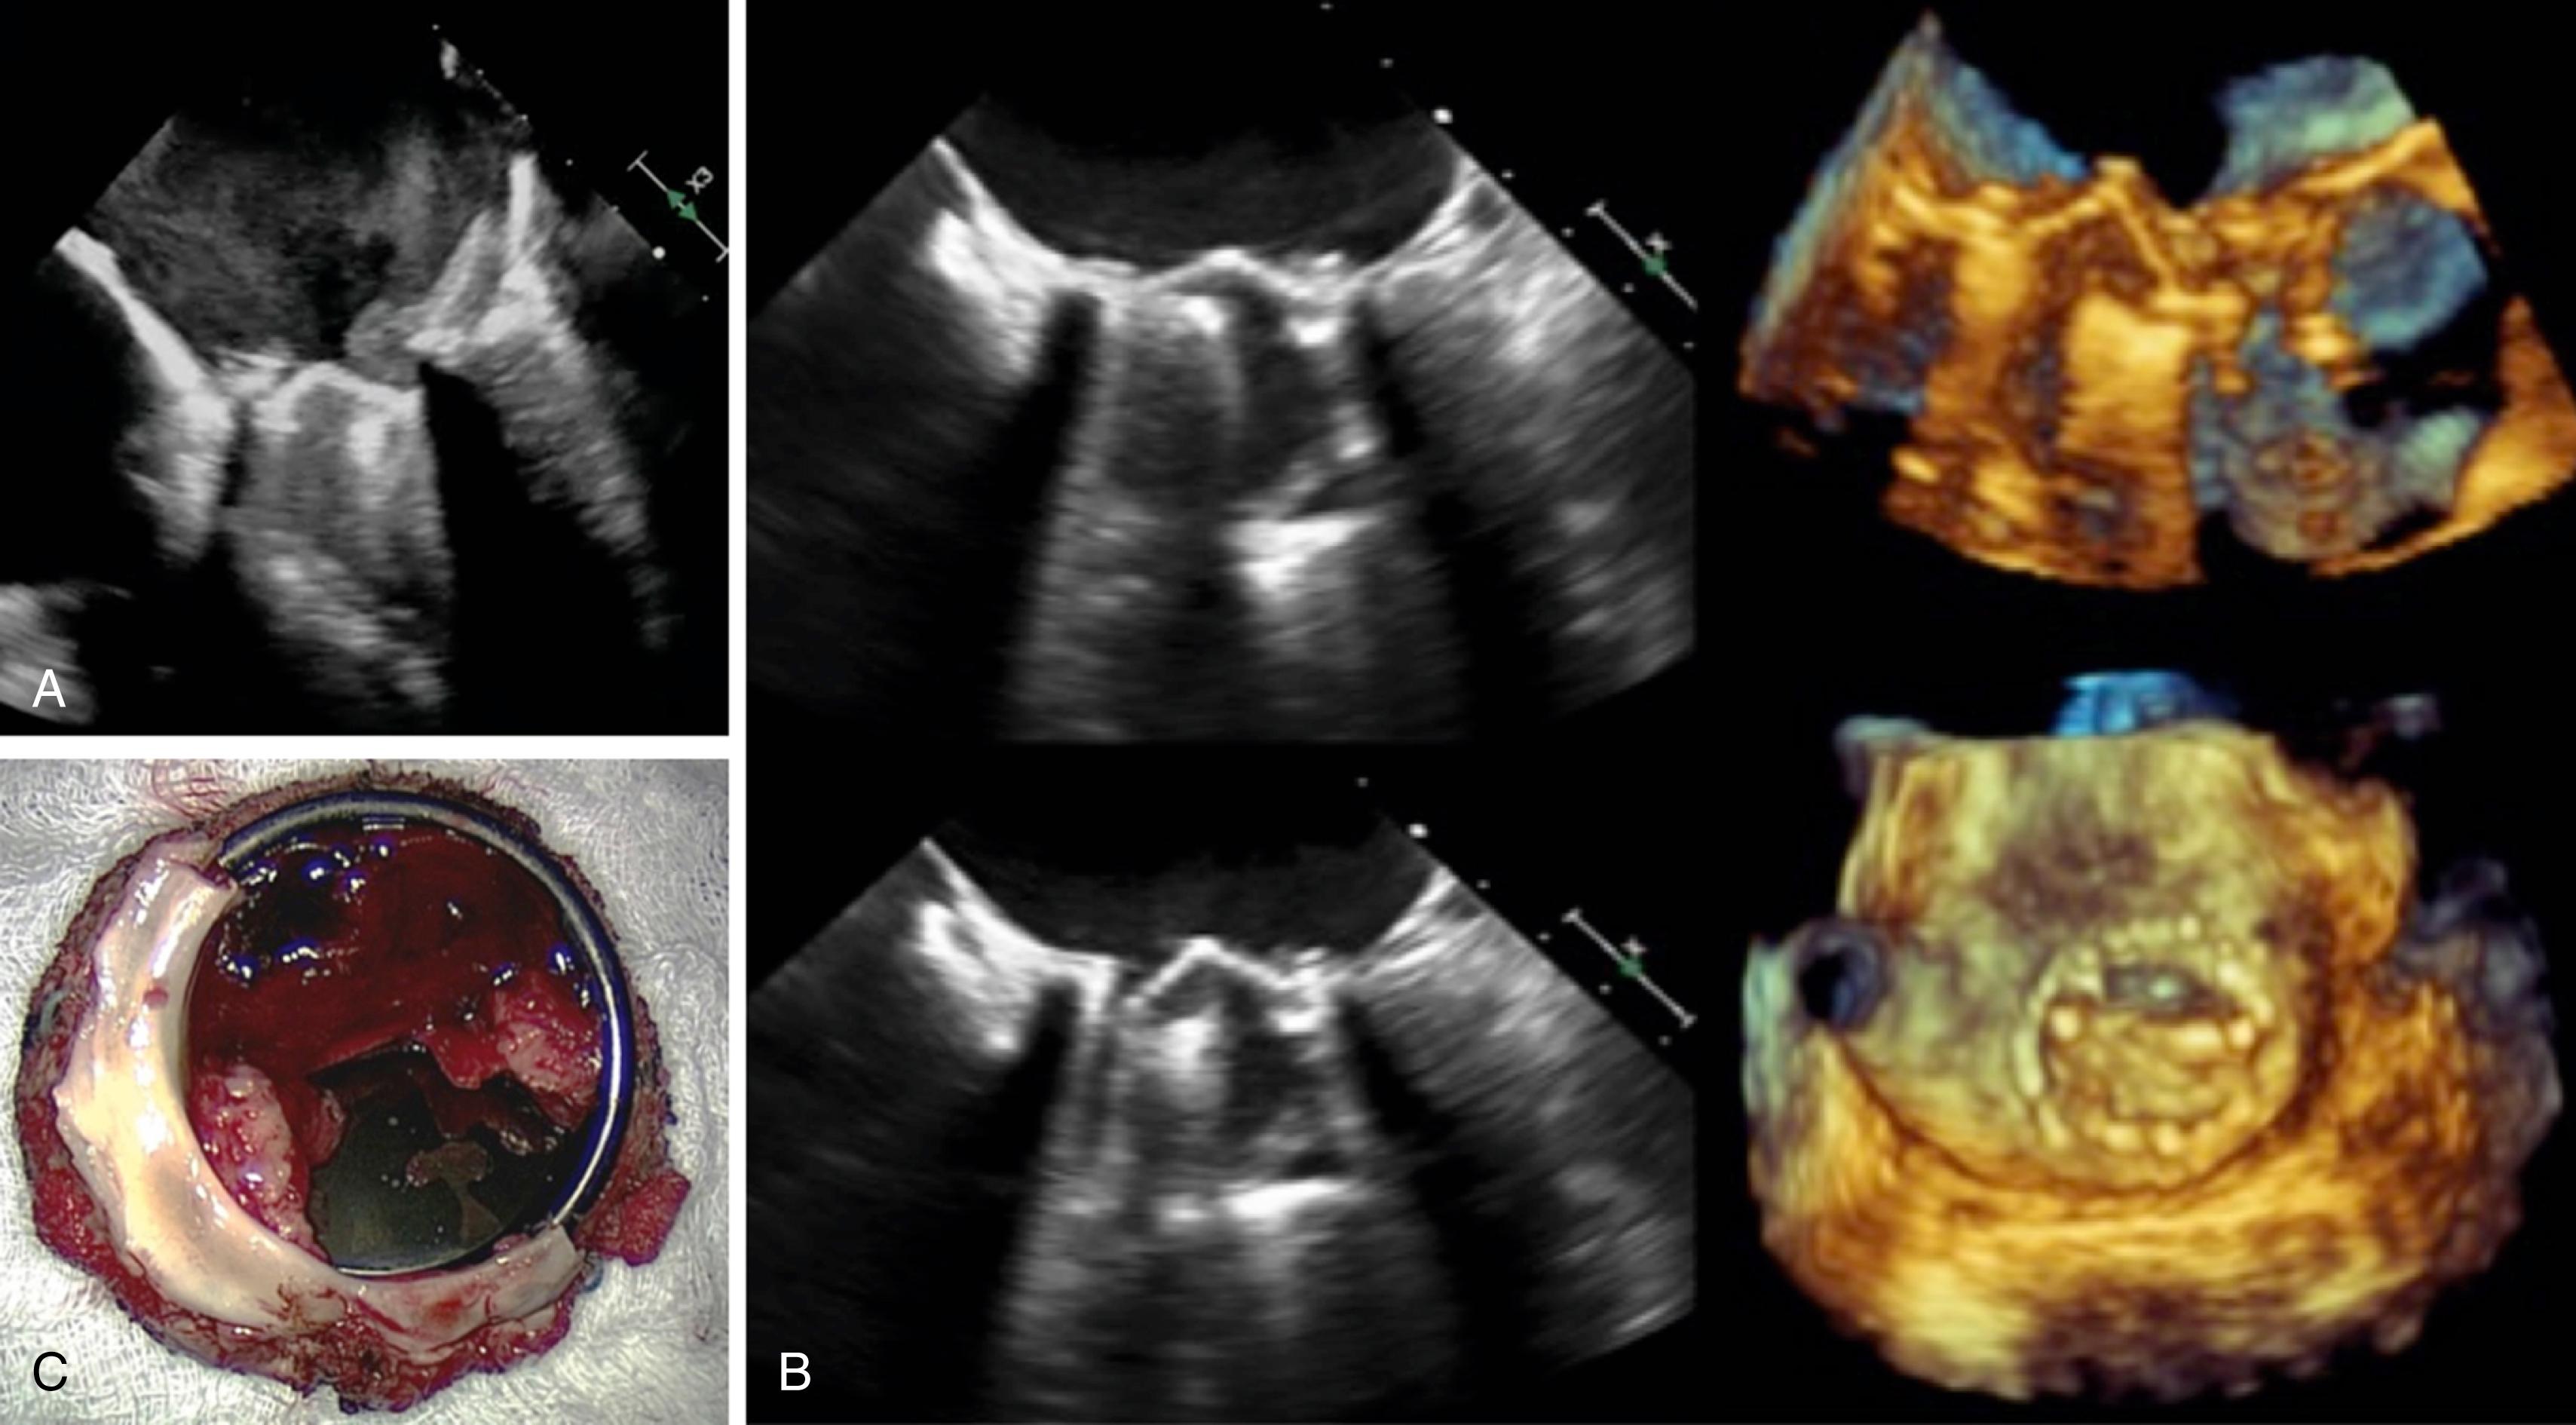

TEE is frequently used for the investigation of suspected or confirmed prosthetic valve dysfunction. Image quality of bioprosthetic and mechanical prosthesis is invariably enhanced by the use of TEE because of less acoustic shadowing and less obscuration of far-field structures. TEE is standardly performed for concern of prosthetic valve endocarditis because of its superior sensitivity and ability to evaluate for vegetation, abscess, or fistulous complications. With 2D and 3D TEE, careful delineation of prosthetic leaflet motion, degenerative changes, and the presence of pathologic thrombus, vegetations, or pannus can be performed, with consequential implications for clinical management ( Fig. 14.5 and , ). The introduction of 3D color imaging with adequate temporal resolution can also help to coregister abnormal regurgitant jets to the valvular or perivalvular space, as well as define the associated lesion severity ( Fig. 14.6 and ). Real-time TEE guidance is now standardly used for percutaneous valve interventions, including perivalvular leak closure.

Figure 14.5, A, Mechanical mitral prosthesis thrombosis with left atrial and valve-associated thrombus and dense spontaneous echo contrast in the left atrium. B, Mechanical mitral prosthesis dysfunction with immobile posterior mechanical leaflet on two- and three-dimensional imaging with pathology demonstrating amalgam of acute and chronic thrombus, with pannus formation ( C ). See accompanying Video 14.5A , Video 14.5B .

Video 14.5 . A, Two-dimensional imaging of a thrombosed mitral valve with dense spontaneous echo contrast layered in the LA. B, Three-dimensional en-face view of the same valve with evidence of stasis in the LA and abnormal leaflet mobility.